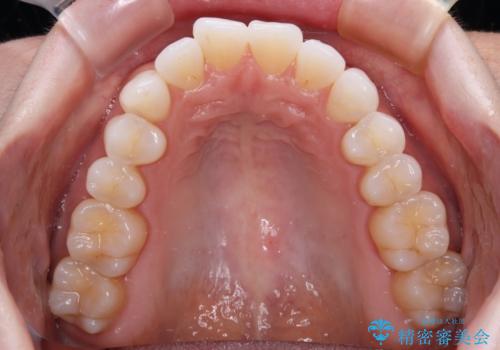

前歯のデコボコをインビザラインで綺麗に

- 上下前歯の叢生を気にして来院された患者様です。

インビザラインでの治療を希望されていて、デコボコの程度が中等度であり、安価なパッケージにて対応可能と判断されたため、インビザライン・モデレートを用いて矯正治療を行うこととしました。

インビザライン・モデレートは、製作できるアライナーの枚数に制限があるため、移動可能な量に限りがあるものの、インビザライン・ライトよりも枚数が多いため、幅広い症例に対応可能です。